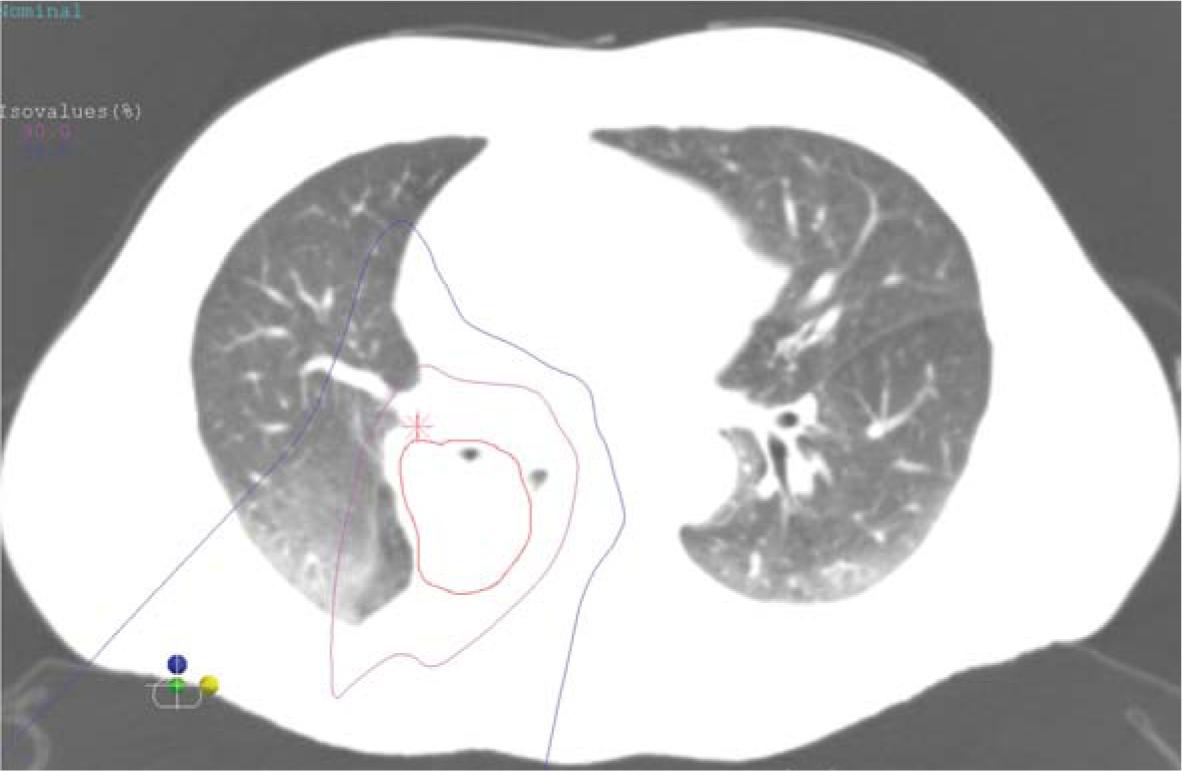

Figure 1